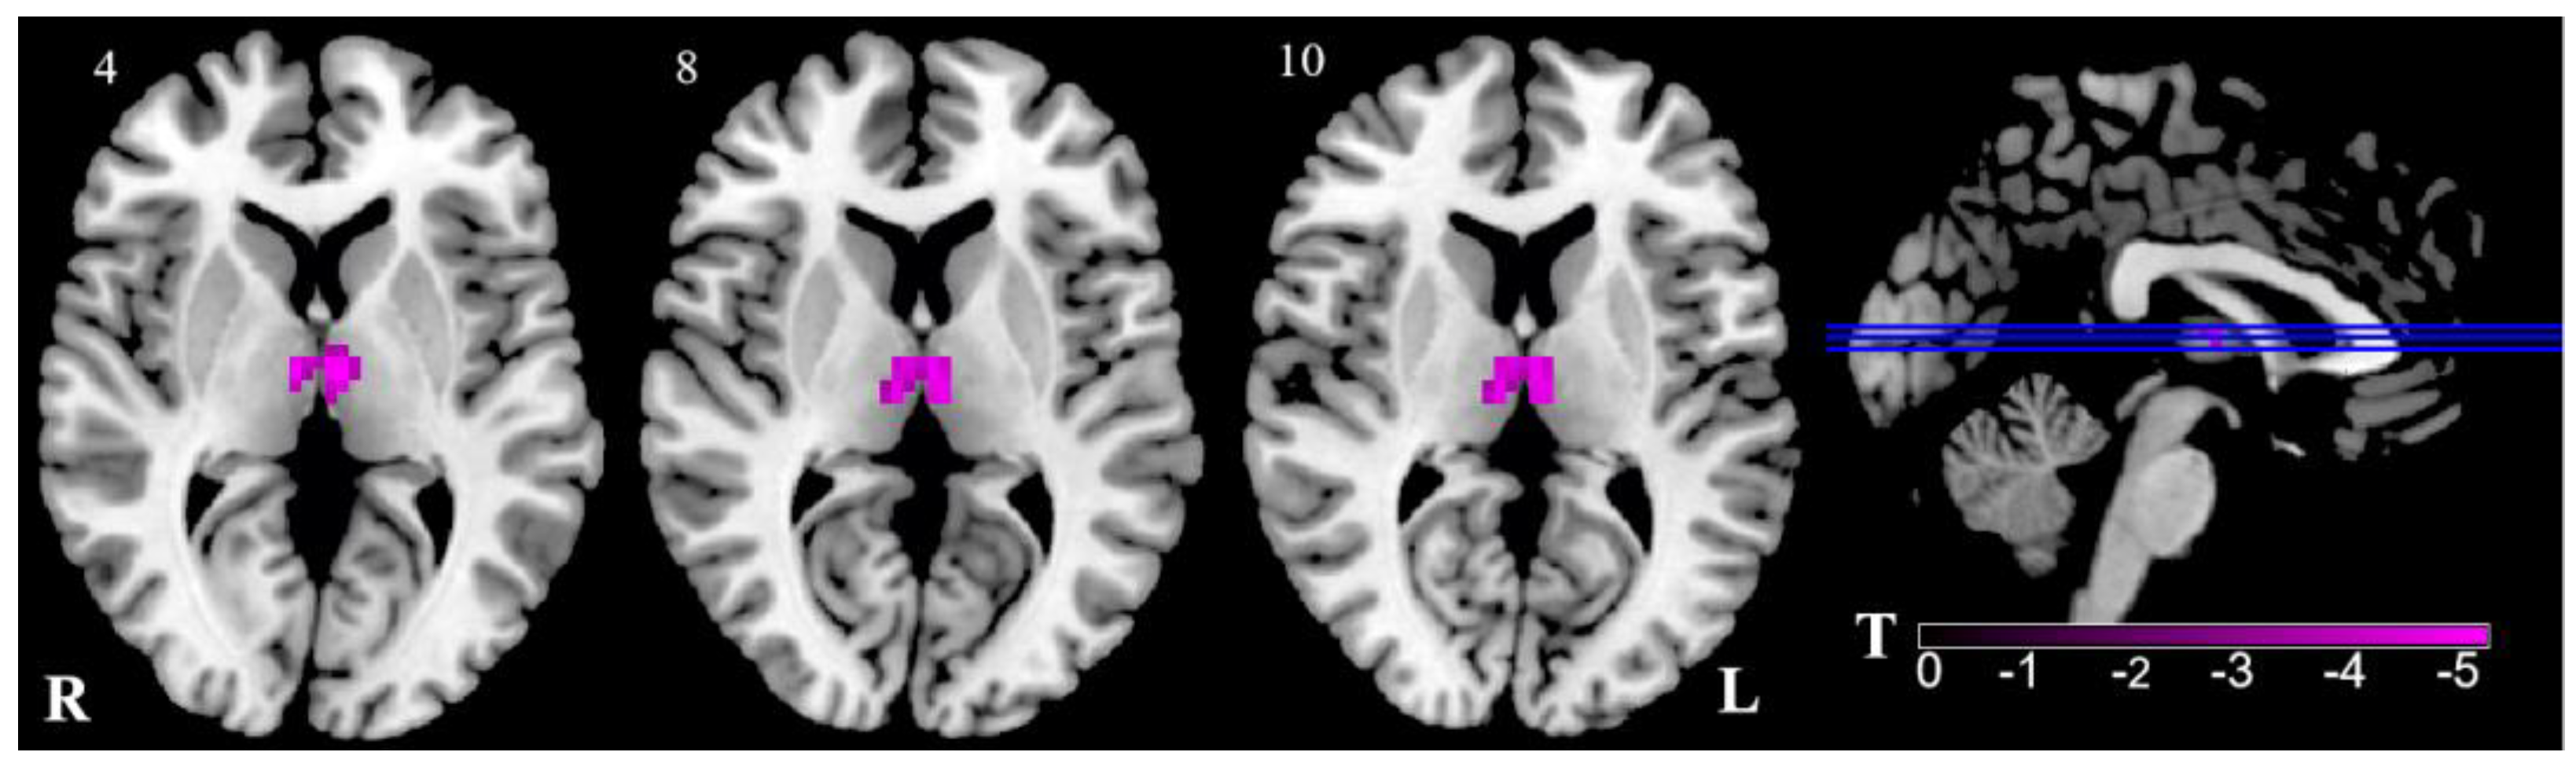

| Brain Regions | Peak MNI | Cluster Voxels | T | p | |||

|---|---|---|---|---|---|---|---|

| x | y | z | |||||

| R | Thalamus | 6 | −12 | 6 | 41 | −4.83 | 0.000 |

| L | Thalamus | −3 | −12 | 6 | 43 | −4.83 | 0.000 |